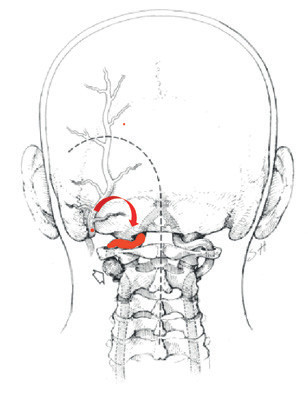

Ze zobrazovacích vyšetření vyplývá, že nemocný má nedostatečnou perfuzi ve VB povodí. Podle studie Veritas jde o „low flow“ pacienta s ročním rizikem opakovaného iktu 22 %.1,2 U těchto pacientů je indikován revaskularizační výkon. Endovaskulární rekanalizace chronického uzávěru vertebrálních tepen nebyla možná, proto jsme se rozhodli provést augmentaci průtoku ve VB povodí pomocí bypassu okcipitální arterie (z povodí a. carotis externa) na horizontální segment vertebrální arterie V3 vlevo. Tímto bypassem jsme plánovali posílit průtok ve vertebrální arterii bypassem z povodí karotidy, obnovit znovu antegrádní tok v bazilární tepně a normalizovat průtok ve VB povodí.

Operace byla provedena v celkové anestezii v poloze na břiše. Po odklopení kožního laloku subokcipitálně vlevo jsme vypreparovali arteria occipitalis a tuto jsme mikrotechnikou „end‑to side“ našili na vertebrální arterii vlevo na oblouku obratle C1 těsně před vstupem do tvrdé pleny (obr. 6, 7). Po sutuře jsme ověřili průchodnost bypassu pomocí dopplerovské ultrasonografie a intraoperační angiografií v operačním mikroskopu po podání ICG (indocyanine green). Pacient se po operačním výkonu rychle zotavil, rána zhojena per primam.